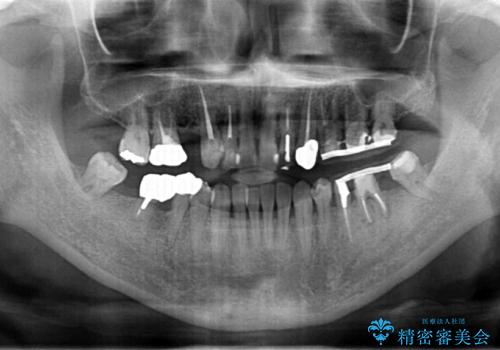

虫歯・噛み合わせ・インプラント、全顎総合治療

- 「歯の見た目が悪く、奥歯も噛みづらい、しっかりと全体的に治療したい。」と全顎的な治療を希望され来院されました。

虫歯・感染根管・予後不良歯・欠損・不正咬合、複合的な問題を一つづつ丁寧に解決し、将来に渡り不安のない口腔内環境にすべく全体的な総合治療を行っていきます。

安定する噛み合わせの位置を探りながらの治療となりました。

最終的に非常に安定した咬合関係を構築できたので、しっかりとどんな食事でも楽しめると同時に、清掃性も高く清潔な口腔内環境を確立できました。